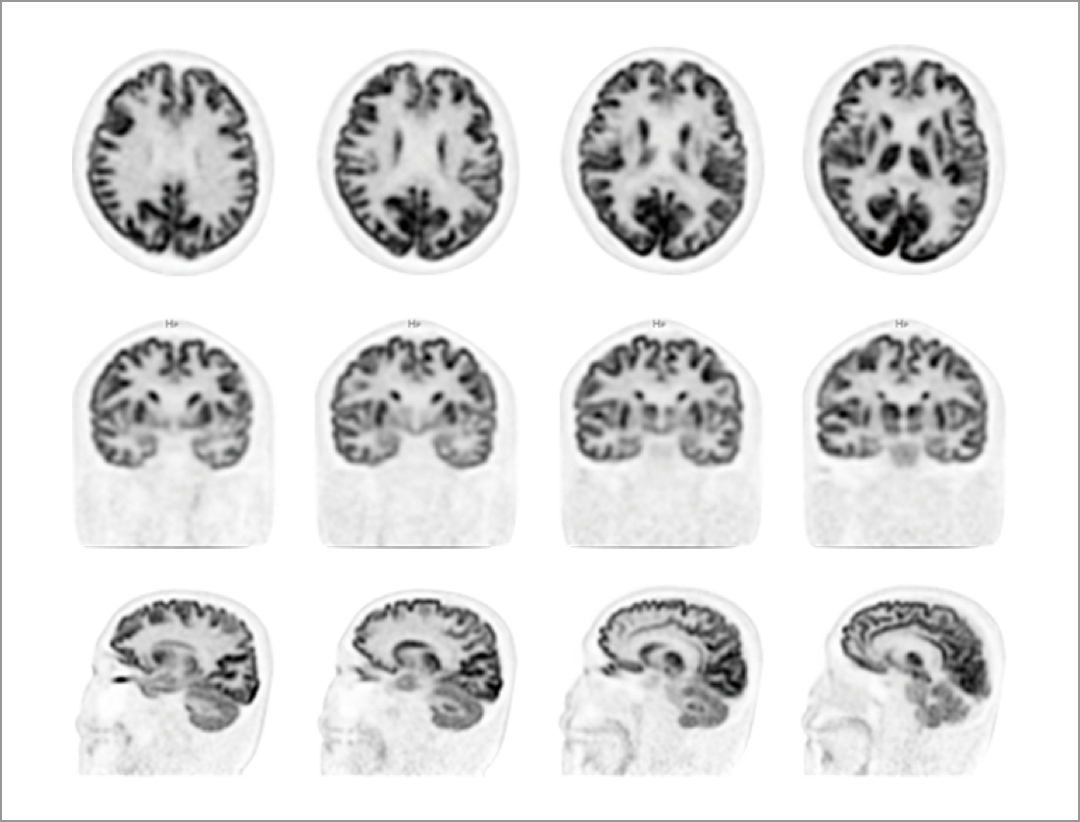

无需外接硬件传感器,扫描中实时监测并校正患者主动及非主动性头动,并对操作者做出提示